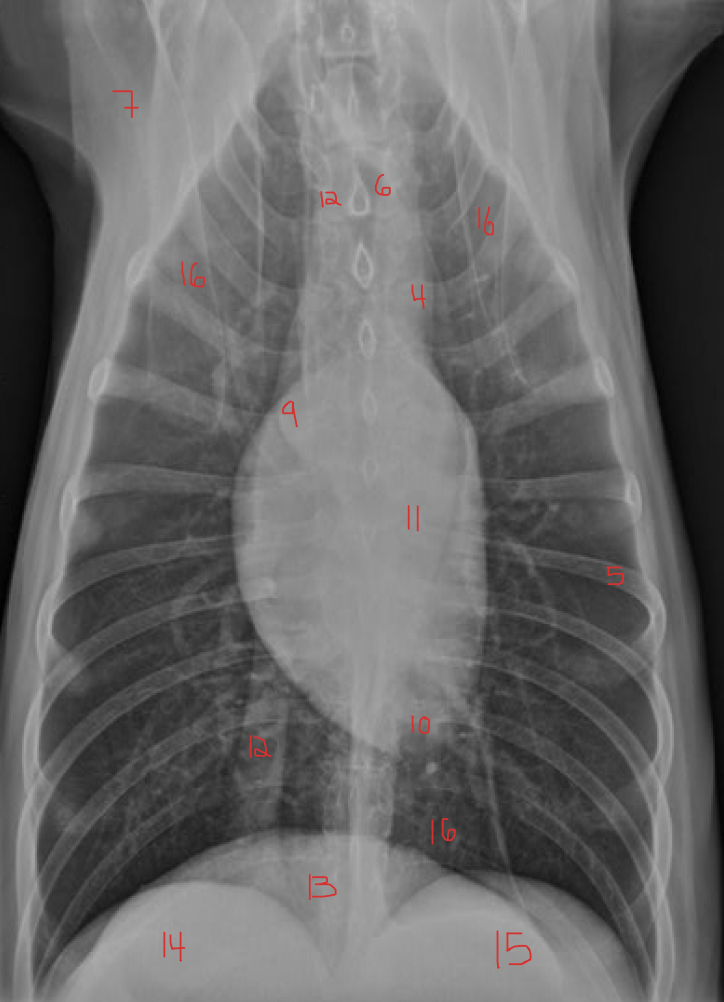

identify the structures

identify the pulomary arteries

identify the aorta

identify the ventral mediastiunum

identify the scapula

identify the ventral lung lobes

Where is the apex of the heart?

towards the left of the midline

why does the heart appear to sit to the left of the midline in this dorsal ventral radiograph

Because of the size of the right lung

Which chamber of the heart gives rise to the ‘apex’ of the heart?

left ventricle

identify A, B and C

A= left atrium

B= right ventricle

C= trachea